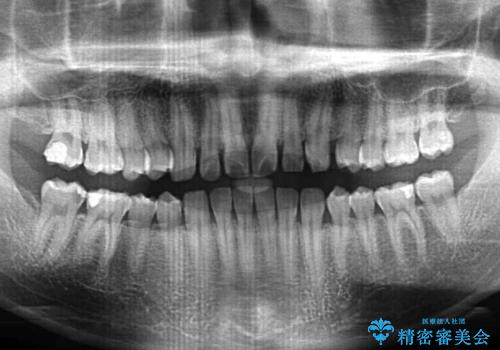

- 前歯がすきっ歯であることを気にして来院された患者様です。

下の前歯がほとんど隠れてしまうくらいの深い咬み合わせであったので、インビザラインを用いて、咬み合わせの高さを改善しながら隙間を閉じていくこととしました。

咬合力で上の前歯が前方に押し出されるようにして隙間ができていましたが、矯正治療により全て閉じることができました。

深い咬み合わせも多少改善され、隙間も閉じたことで、前方に出ていた前歯が引っ込んだため、口も閉じやすくなったとのことでした。